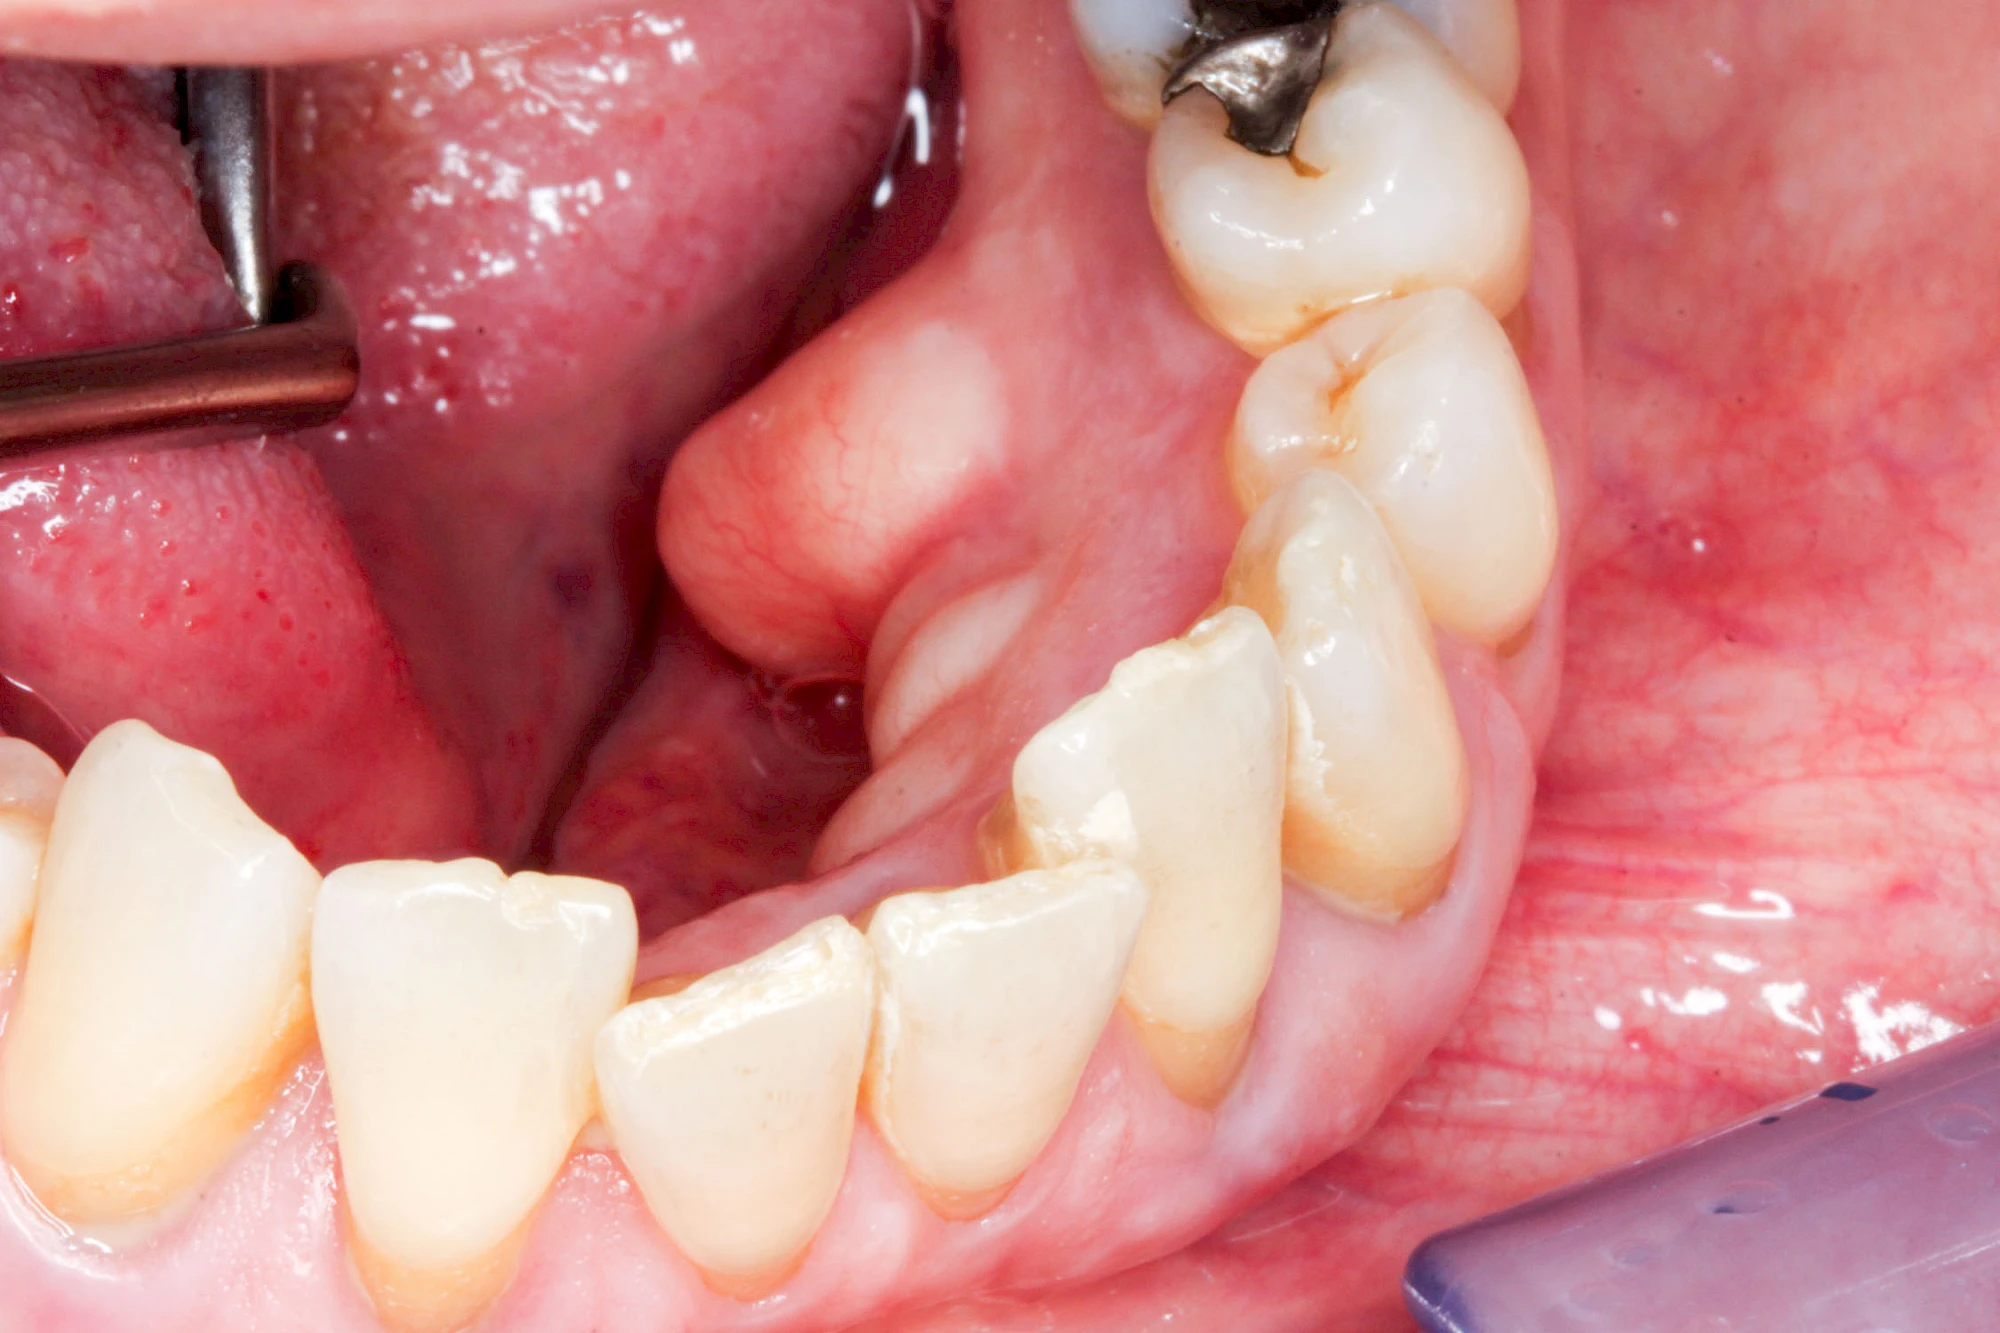

Heute werden in Deutschland Menschen mit Lippen-Kiefer-Gaumenspalten bereits ab Geburt von Experten verschiedener Fachrichtungen (Mund-Kiefer-Gesichtschirurgen, Kieferorthopäden, Logopäden) betreut, damit entsprechende Korrekturen schon frühzeitig erfolgen können. Gerade jedoch bei älteren Menschen ist dies nicht immer geschehen. Diese Menschen tragen häufig technisch aufwendige Zahnprothesen.